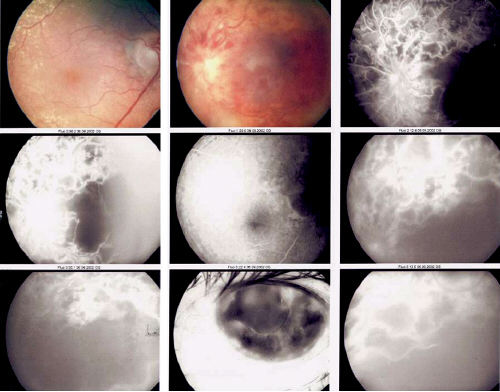

This is the fluorescence angiography of a patient with poor left vision (The patient also has bilateral nuclear sclerosis). a. What is the diagnosis? b. What abnormalities are shown by the fluorescein angiogram?

Answer a A left central retinal vein occlusion. Answer b The fluorescein angiography show the following abnormalities: 1. Retinal ischaemia note areas of hypofluorescence 2. Neovascularization in the peripheral retina note areas of hyperfluorescence 3. Rubeosis iridis shown by iris hyperfluorescence. This patient has ischaemic central retinal vein occlusion resulting in retinal neovascularization and rubeosis iridis.